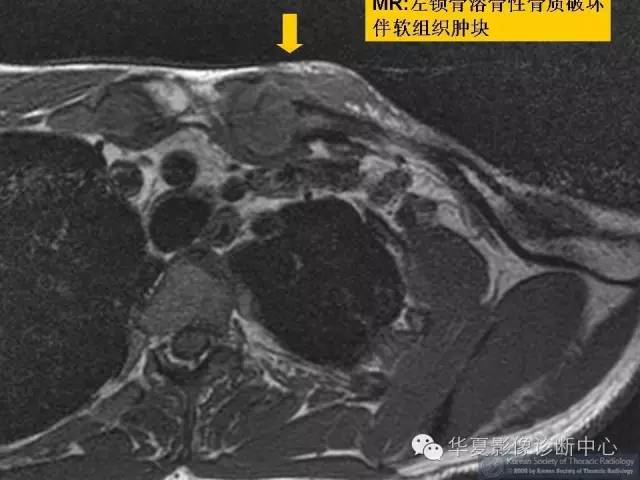

肺转移瘤的十种不典型CT表现